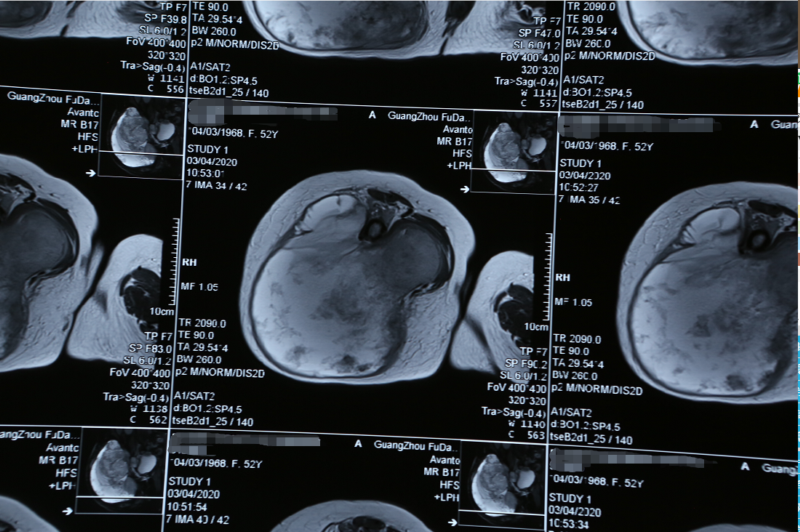

這是一位50多歲的菲律賓女性患者,15個月前發(fā)現(xiàn)患有右側臀部軟骨肉瘤,之后很快增大蔓延到整個右臀部和大腿后外側導致大腿浮腫無法行走。曾經(jīng)在馬尼拉3家醫(yī)院多次輾轉求治,連菲律賓最好的外科醫(yī)生們也都搖搖頭表示無法治療,最后患者在當?shù)亟邮芊呕熤委熜Ч跷⑥D至我院。由于腫瘤及淋巴互相融合包裹著血管干,手術難度非常大、風險極高,為盡可能保住患者的腿部,穆峰副院長聯(lián)手南方醫(yī)科大學的覃承和教授為患者制定合適的治療方案。

此時已是下午13點25分,腫瘤被完整分離,保護皮瓣血管網(wǎng),吸取部分的腫瘤壞死液化,止血,仔細探查分離已經(jīng)被腫瘤侵犯的坐骨神經(jīng),整塊切除腫瘤和被腫瘤侵犯的股骨大轉子和部分骨盆壁。通過測量得知腫瘤大小為38*36*28cm,90%為實性,腫瘤重達約6Kg,其中抽取的囊液約2Kg。該患者原發(fā)于右臂骨盆,侵透骨盆進入盆腔6*7*8cm;右臂肌深面軟骨肉瘤上延伸至髂嵴下至大腿后外側上三分之一共38cm,前后寬度32cm,厚度28cm;侵犯股骨大轉子和坐骨神經(jīng)長約10cm。當穆副院長看到腫瘤已嚴重侵入盆骨后采用“刮骨療傷”法,用手術刀輕輕刮去依附在骨頭上及粘附在其他周圍的腫瘤組織,切除進入盆腔8.0*6.5*5.8cm腫瘤達到了肉眼徹底整塊切除肉瘤的效果。